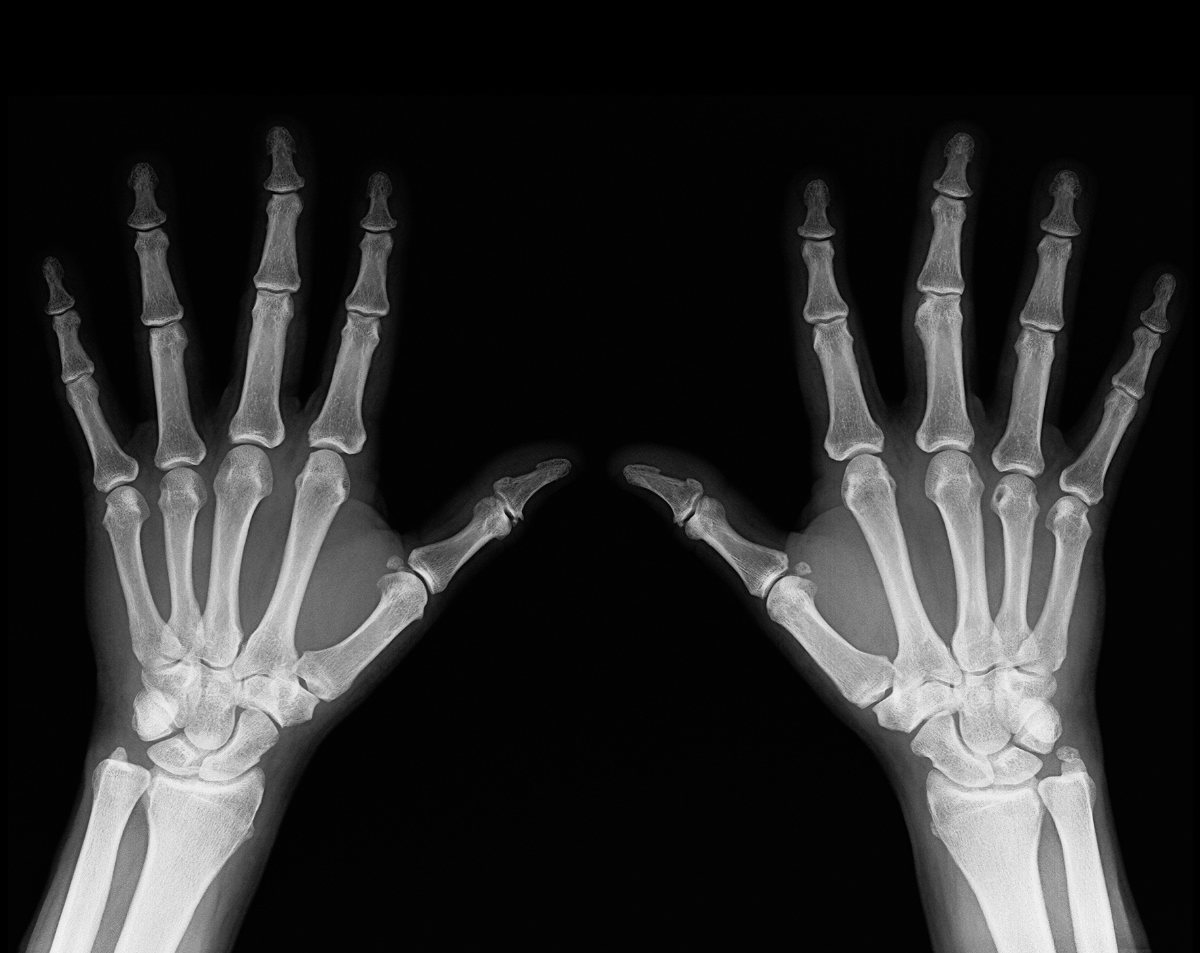

A mobile finger X-ray provides sharp, detailed images that help physicians quickly identify the root cause of your symptoms. For example, it can detect:

Fractures and breaks from accidents, falls, or sports injuries

Dislocations affecting finger joints

Arthritis changes causing stiffness or swelling

Infections or bone damage that weaken the structure

Tumors or cysts within the bones of the fingers

Healing progress after surgery or treatment